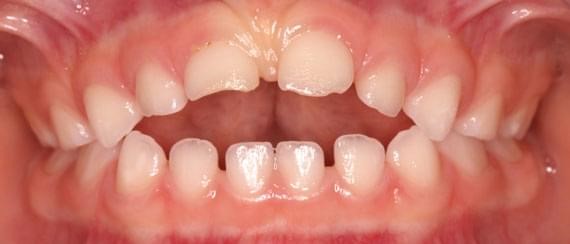

Khớp cắn chéo quá sâu có thể tình cờ gây ra loét mô mềm, những trường hợp này nhu cầu thẩm mỹ thì nhỏ nhưng vấn đề loại bỏ nguyên nhân gây chấn thương mô mềm thì lớn. Ai nên được điều trị chỉnh nha? Phần lớn điều trị chỉnh nha được tiến hành vì nhu cầu thẩm mỹ và lợi ích mà mỗi bệnh nhân nhận được từ việc điều trị sẽ phụ thuộc vào mức độ trầm trọng của mức độ sai khớp cắn và nhận thức của bệnh nhân về vấn đề này. Một số cá nhân có thể có sự lệch lạc ở mức độ quá rõ ràng làm ảnh hưởng trầm trọng tới gương mặt của họ tuy nhiên họ cũng chẳng quan tâm đến và không cần điều trị nếu bác sỹ không có cách thuyết phục. Bác sĩ lâm sàng có thể đưa ra lời khuyên về phương pháp điều trị cho bệnh nhân nhưng cũng không nên yêu cầu họ một cách cứng nhắc mà nên để cho họ có thời gian ngồi lại và suy nghĩ để đưa ra quyết định cuối cùng hợp tác với bác sỹ điều trị. Lệch lạc khớp cắn mức độ nhẹ nên được điều trị với sự cẩn trọng vì khả năng tái phát sau khi điều trị. Các bậc phụ huynh có thể có rất nhiều yêu cầu khác nhau nhưng các bác sĩ lâm sàng nên tiếp cận những vấn đề này một cách cẩn trọng và chỉ tiến hành điều trị khi nó đem lại lợi ích tốt nhất cho bệnh nhân. Điều thiết yếu nhất cần nhớ là phụ huynh và bác sĩ cần phải nhận thức rõ về những hạn chế cũng như sự đòi hỏi nhiều thời gian của việc điều trị chỉnh nha. Kế hoạch điều trị nắn chỉnh răng Trong quá trình phát triển của bộ răng người, có thể chia làm ba giai đoạn chính như sau: giai đoạn răng sữa, giai đoạn răng hỗn hợp và giai đoạn răng vĩnh viễn. Sau đây là một số gợi ý những trường hợp nào cần và nên điều trị theo các giai đoạn của bộ răng: Kế hoạch điều trị ở hàm răng sữa Lý do điều trị: điều trị nắn chỉnh răng ở hàm răng sữa vì lý do sau: (1) loại bỏ các cản trở đến sự tăng trưởng bình thường của mặt và cung răng. (2) duy trì hoặc phục hồi lại chức năng bình thường Các trường hợp cần phải điều trị: a) Cắn chéo phía trước và sau.